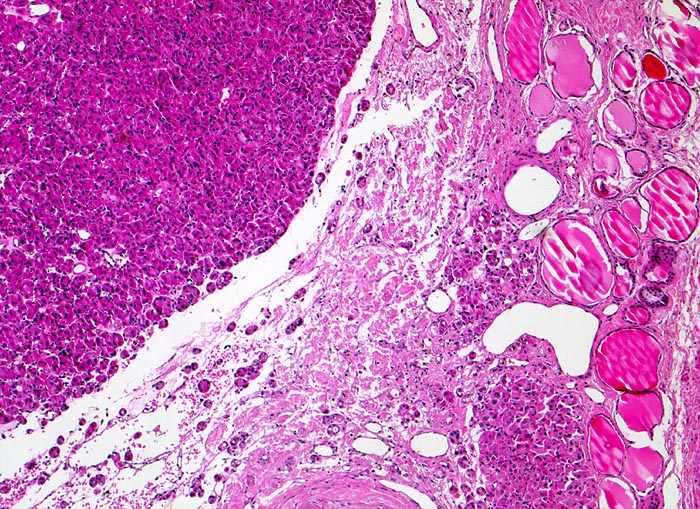

• Kapseldurchbrüche: Die breite bindegewebige Kapsel wird an mehreren Stellen pilzförmig vorgewölbt und an einigen Orten vollständig durchbrochen.

• Keine eindeutigen Gefässeinbrüche (keine Tumorthromben oder endothelialisierte Tumorzapfen in Venen der Kapsel oder jenseits der Kapsel). Das sollte der Kliniker dem Pathologen mitteilen:

Entscheidend für die Diagnose eines follikulären Schilddrüsenkarzinoms in Abgrenzung zu einem gutartigen follikulären Schilddrüsenadenom ist der Nachweis eines Durchbruchs der Tumorkapsel (> 2753) (> 4951) und/oder ein Einbruch in Venen (> 4953) (> 8265) innerhalb oder jenseits der Tumorkapsel sowie das Fehlen morphologischer Kernmerkmale eines papillären Schilddrüsenkarzinoms. Zytologische Atypien kommen auch bei gutartigen follikulären Adenomen vor und sind deshalb kein Malignitätsmerkmal. Da Kapseldurchbrüche und Gefässeinbrüche nur am Gewebsschnitt diagnostiziert werden können, ist eine präoperative zytologische Diagnose eines follikulären Schilddrüsenkarzinoms anhand der Feinnadelpunktionszytologie nicht möglich.